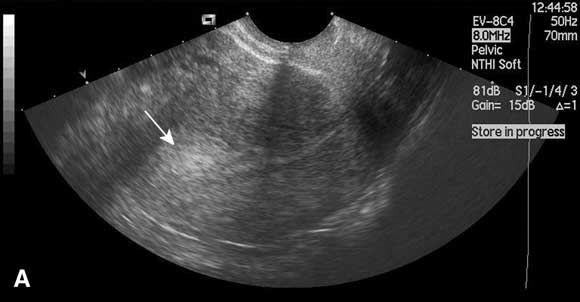

In this case, saline infusion sonohysterography confirmed the presence of a submucous fibroid. This was resected hysteroscopically under general anaesthesia, leading to a substantial reduction in menstrual bleeding and a reduction in dysmenorrhoea.

In this technique, saline is instilled transcervically into the uterine cavity to distend the uterus and increase contrast, and the cavity is visualised using ultrasound (Box). Saline infusion sonohysterography is more accurate than transvaginal ultrasound alone in diagnosing submucous fibroids and endometrial polyps in women with abnormal uterine bleeding,12 and can be performed in the outpatient clinic. An alternative form of imaging is diagnostic hysteroscopy, but this is invasive and often performed under general anaesthesia. Use of saline infusion sonohysterography has been shown to reduce the need for diagnostic hysteroscopy.13